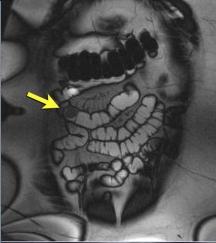

Polyp adenomateux : ( Image IRM T2 fat

sat ) Masse arrondie a iso-signal de l'intestin (

fleche jaune ) a limite net et a bord lisse . |